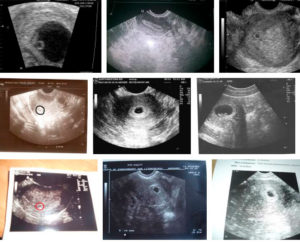

На таком сроке проводят ультразвуковой мониторинг с целью определения наступления овуляции. После менструации каждые 2-3 дня врач наблюдает за созреванием фолликулов и выходом яйцеклетки. На УЗИ определяется желтое тело.

Овуляция на УЗИ

Чаще всего на таком сроке беременности УЗИ не требуется, разве что есть необходимость оценить готовность эндометрия к зачатию. Аппарат в этот момент сможет исследовать и распознать доминирующий фолликул, но разглядеть яйцеклетку нет возможности.

Пройти такое обследование могут женщины, у которых уже были проблемы с зачатием, но планируют на данный момент беременность.

- УЗИ-мониторинг (ультразвуковой мониторинг). Самый достоверный метод определения выхода зрелой яйцеклетки из фолликула яичника, к которому в настоящее время прибегают многие женщины, планирующие беременность. При УЗИ-мониторинге можно назвать предположительный срок наступления овуляции, а не просто сделать вывод, что сегодня ее нет и вы уже опоздали. При нерегулярных циклах данный метод также помогает выявить причины задержки.